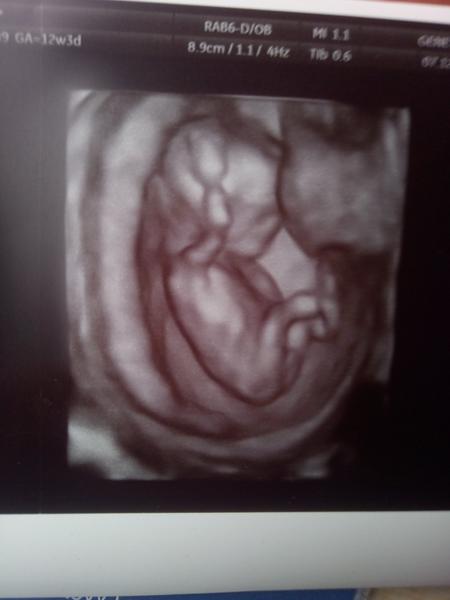

Je to tutový chlapeček?

Já si myslím,že je to kluk jak vyšitý.